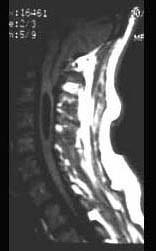

问题 该头颅MRI摄片提示 ( )

选项 A、寰枕融合 B、无脑畸形 C、扁平颅底 D、Arnold-Chiari畸形 E、小脑扁桃体肿瘤 单选题

答案 D